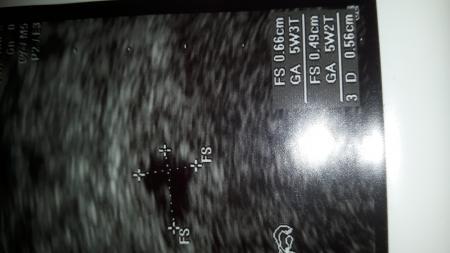

Sind das die Größe der Fruchthöhle? Wie groß müsste der Embryo sein? Sorgt für die dumme Frage

FS ist der Fruchtsack und GA ist die SSW, die mit den Maßen ausgerechnet wurde. der Embryo ist in der 6. SSW erst wenige mm

Danke jetzt weiß ich endlich was FS auf dem Bild heißt